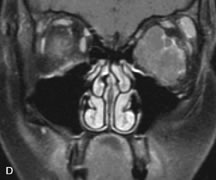

Inflammatory conditions of the orbit, both idiopathic (inflammatory pseudotumor) and those of known causes, have been found to be hypointense to fat and isointense to muscle on Tl-weighted studies and isointense or slightly hyperintense to fat on T2-weighted images (Fig. 21).50,64,69 The more fibrous or sclerosing varieties have less signal intensity on T2-weighted images. Marked enhancement is seen in pseudotumor infiltrates after gadolinium administration.70 The same signal characteristics are demonstrated in patients with Tolosa-Hunt syndrome, with mass lesions seen in the cavernous sinuses and orbital apices.71

Fig. 21. A. T1-weighted MR scan demonstrates diffuse enlargement of both the superior rectus and levator palpebrae superioris muscles (single arrows). The involvement of the tendinous insertions and preseptal soft tissues (open arrows) as well as lack of involvement of other muscles helps differentiate this entity from thyroid-associated orbitopathy. B and C. Postcontrast fat-suppressed T1-weighted MR scans demonstrate extensive enhancement of the involved muscles as well as the preseptal (open arrows) and perinuscular tissues (double arrows).